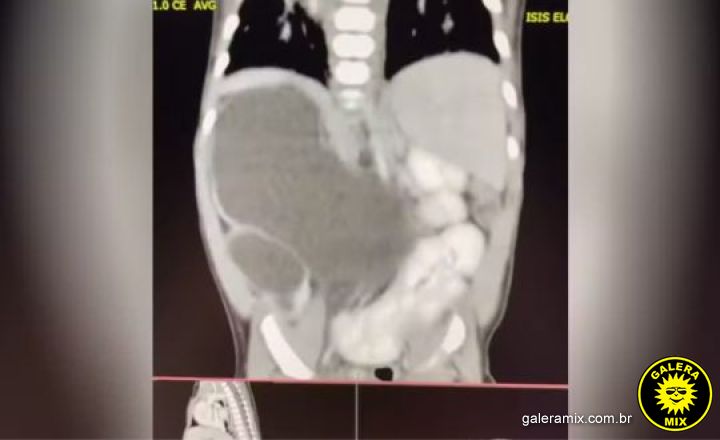

Isis Eloah Ferreira Alves, uma menina de 1 ano e 1 mês de Formosa, Goiás, nasceu com uma condição extremamente rara: quatro rins. O caso, que é um dos cerca de 100 documentados na literatura médica mundial, é conhecido como “rins supranumerários” e requer acompanhamento médico contínuo.

Aos cinco meses de idade, durante uma cirurgia, os médicos confirmaram a presença dos quatro rins em Isis. Atualmente, ela recebe tratamento no Hospital da Criança de Brasília (HCB), localizado a cerca de 80 quilômetros de Formosa.